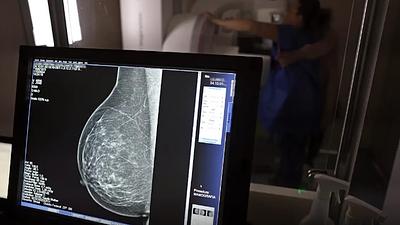

medico.jpg

AGU processa médico que apontou mamografia como causadora de câncer

20/03/2025, 14:42

A AGU pede que o médico seja condenado a pagar R$ 300 mil em indenização por danos morais coletivos, por ter disseminado informação de saúde falsa.